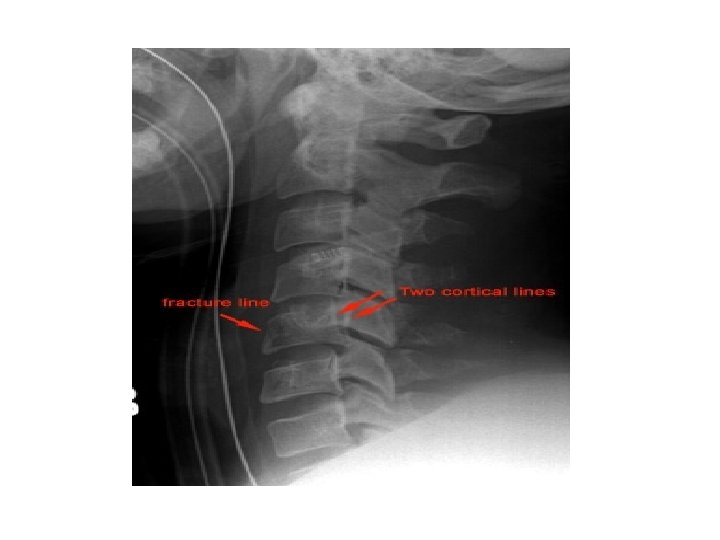

CLAY SHOVELLER’S FRACTURE • Fracture of spinous process C 6 -T 1 • Mechanism – powerful hyperflexion, usually combined with contraction of paraspinous muscles pulling on spinous processes (e. g. shovelling). Features – spinous process fracture on lateral view Ghost sign on AP – double spinous process of C 6/C 7 due to displaced fractured spinous process